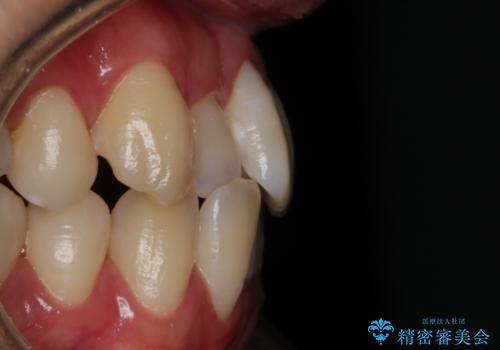

【非抜歯】八重歯を治す マウスピース矯正

- 前歯のガタつきの治療を主訴にご来院されました。

目立たない装置をとのご要望があったため、検査結果をふまえてインビザラインでの非抜歯矯正を行うこととなりました。

非抜歯での治療

抜歯をせずに歯のガタつきを治すためのスペースを作るために

①歯の遠心移動

②歯列弓の拡大

③IPR(歯を少し小さく削る)

この3つの方法を複合的に組み合わせて治療を行いました。

抜歯をせずとも笑った時の歯の見え方が劇的に変化していることが分かります。